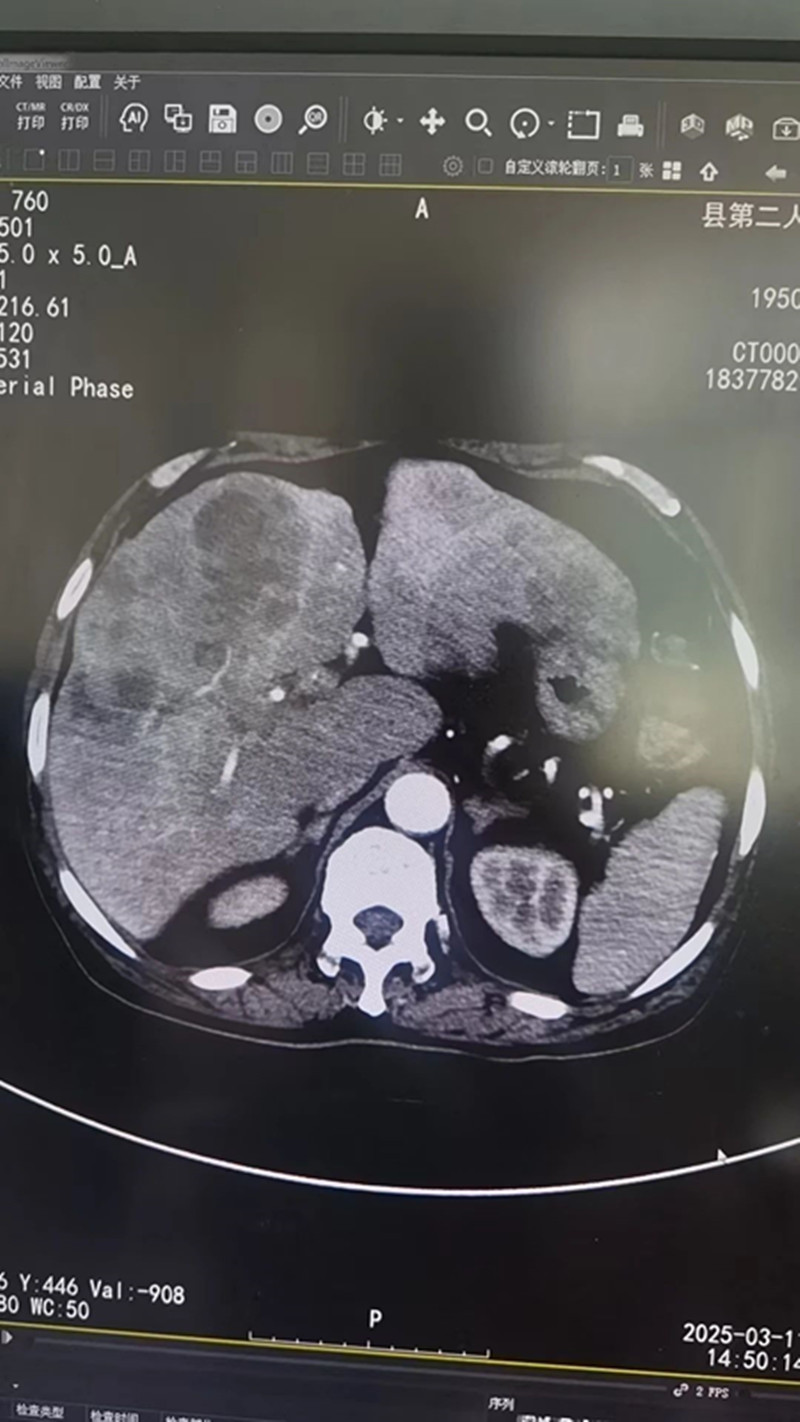

据了解,该患者男,74岁,直肠癌伴肝转移1年余,既往有高血压、慢性胃炎、前列腺增生病史多年。入院后,县二院肿瘤内科副主任医师陶黎明在充分评估患者状况,排除所有手术禁忌证,并获得患者及家属的充分理解并征得同意后,遂施行经导管肝动脉化疗栓塞术(TACE术)。手术过程顺利,实现对肿瘤的“精准打击”,患者术后生命体征平稳,恢复良好。

经导管肝动脉化疗栓塞术(TACE)是一种微创介入治疗技术,通过微小的创口,经导管将化疗药物和栓塞剂直接注入肿瘤供血动脉,从而达到抑制肿瘤生长和缓解症状的目的。该手术有效避免了传统开放手术的创伤和并发症。因此具有“微创、精准、安全、高效”的优点。